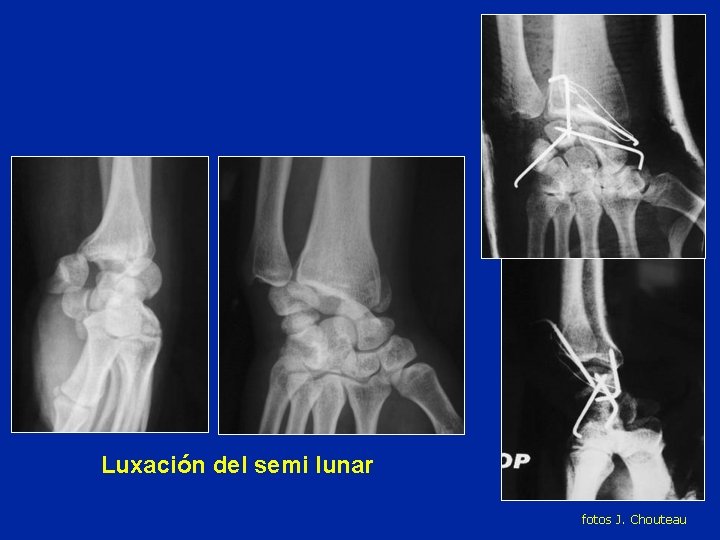

Luxación del semi lunar fotos J. Chouteau

Luxación del semi lunar Riesgo de necrosis